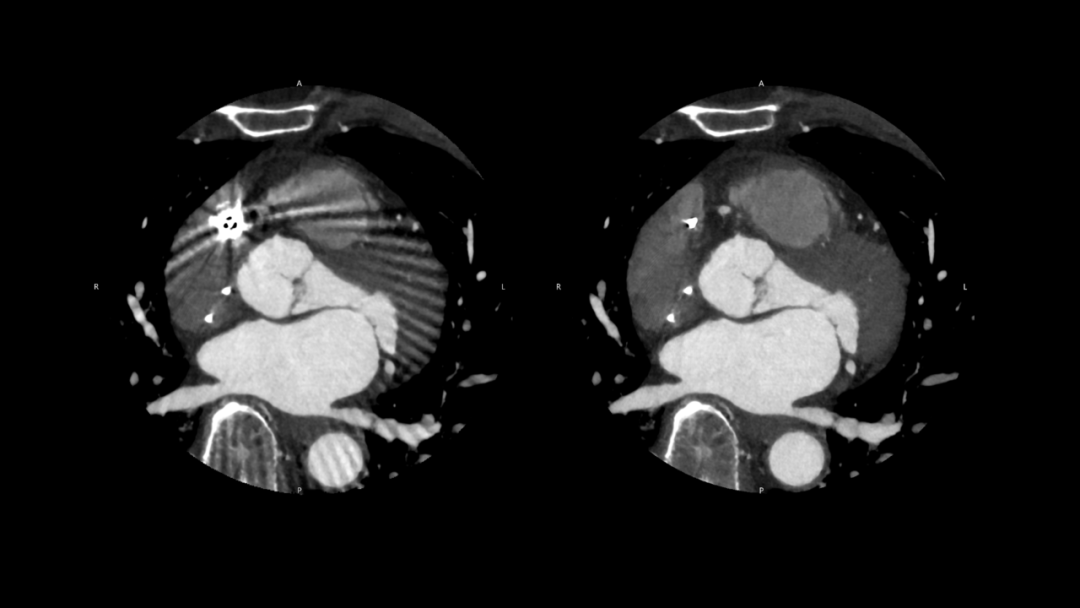

🔹PIQE(Precise IQ Engine)

重塑心脏成像

图片

SEMAR OFF

SEMAR ON

心血管成像中,针对支架、起搏器等金属植入物带来的伪影影响,结合PIQE超分辨重建与SEMAR金属伪影抑制技术,可在不增加辐射剂量的前提下减少金属伪影对图像的影响,提升周围软组织的显示效果,从而为复杂病例提供更清晰、可靠的影像参考。